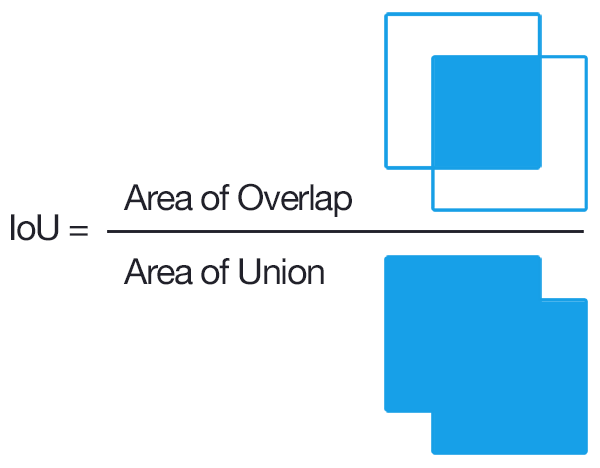

IoU_Score (Intersection over Union):

so we have talked about loss, but what about Evaluation Metrics, should we use Accuracy ???

so Answer is No, for Image Segmenation or Object Localization task IoU_score is being Used extensively ,

Basically Accuracy function will also take those region/pixels which is not part of that object in specific image , specially for medical image segmentation task in which targeted mask contains very less amount of pixel , so in that case accuracy will always be high without taking care about location of the affected region by disease,

after looking at this diagram , you would have get the idea about how IoU Score works ,

It comes in handy when you’re measuring how close an annotation or test output lines up with the ground truth. As a ratio of the areas of intersection and union, it works on annotations of all shapes and size.

What’s cool is how IOU can be used with F1 scores to measure the accuracy of object detection tasks with multiple annotations per image

so after set the loss and evaluation matrice , we train this model using adam as an optimiser for 40 epochs,

so after 40 epochs of training we were able to get 0.73 IoU_Score and 0.71 val_IoU_Score.